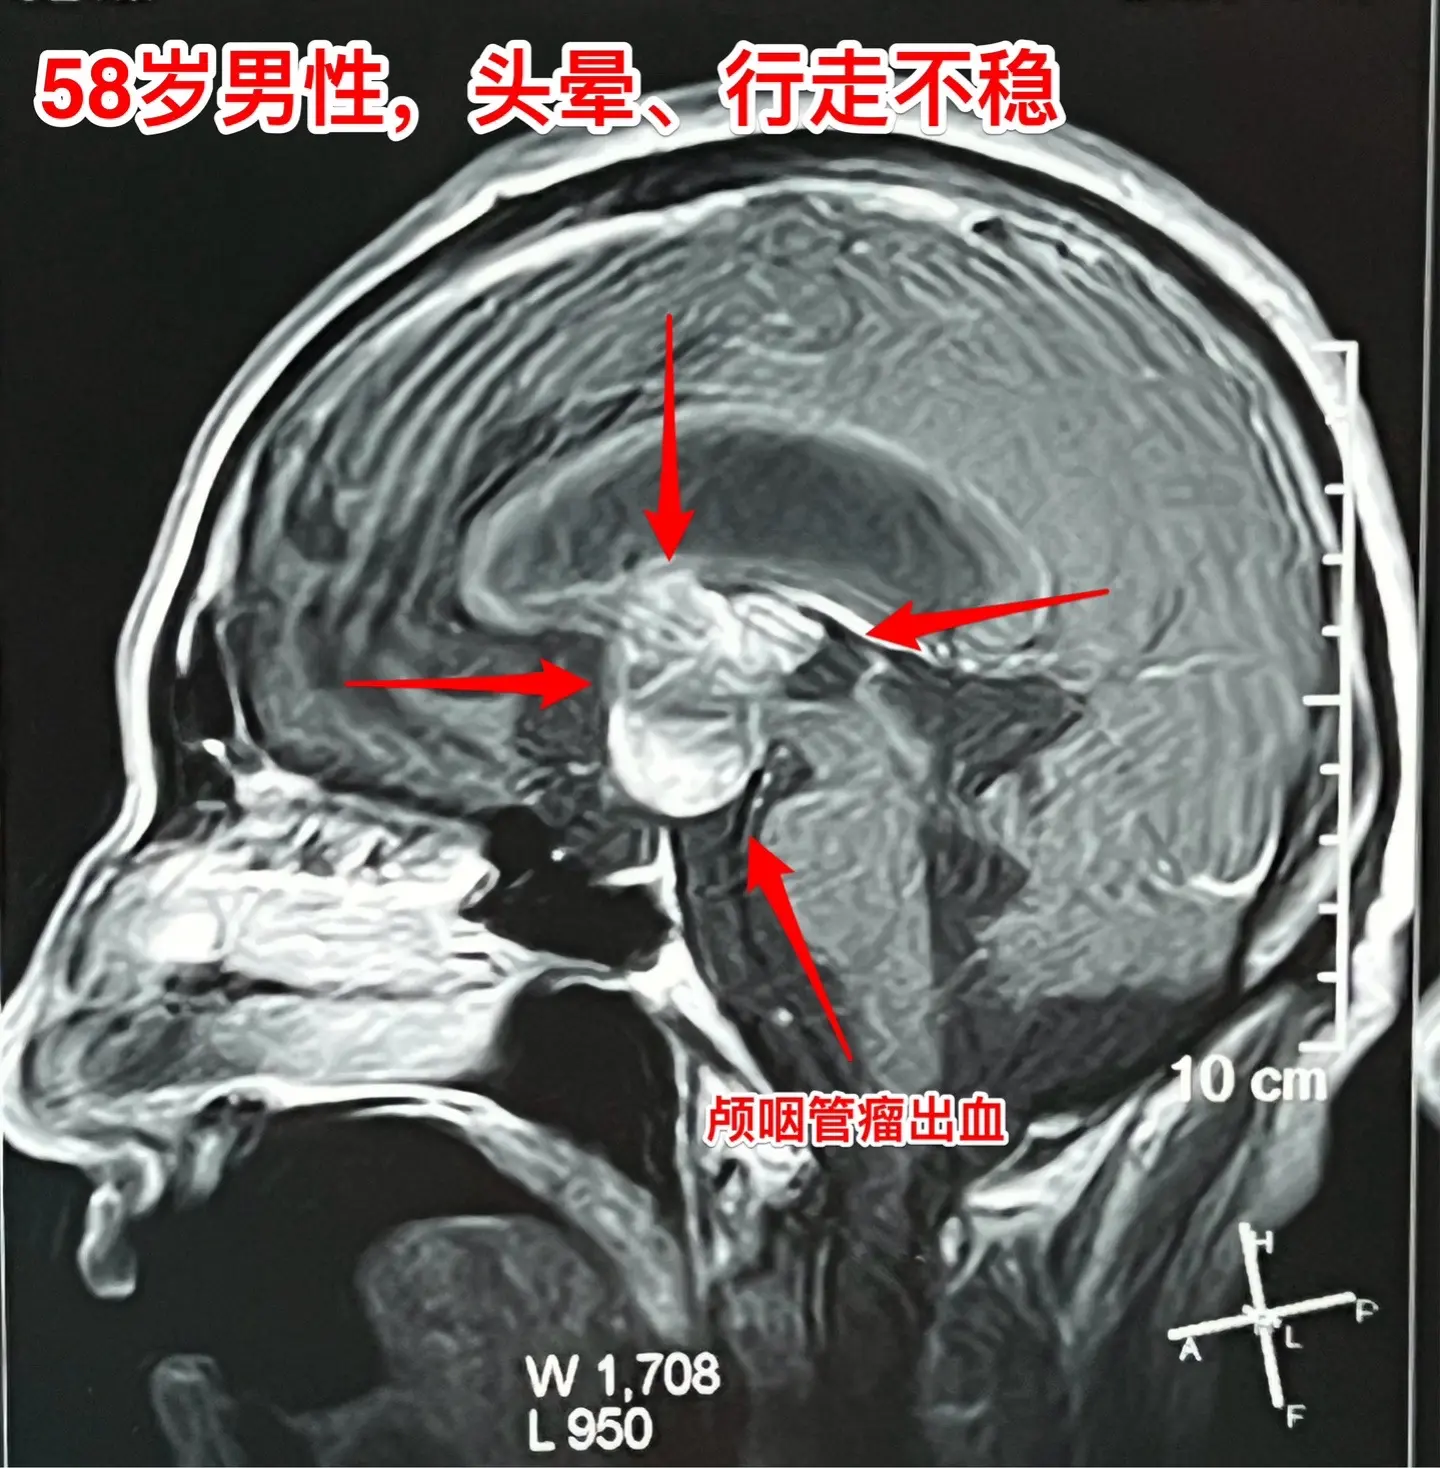

颅咽管瘤内出血(瘤卒中)属于罕见现象。有些脑部肿瘤容易出血,称之为瘤卒中,比如垂体瘤(属于良性肿瘤)和高级别胶质瘤,而颅咽管瘤发生瘤卒中的可能性却很小很小。 58岁的南通市男性,九年前体检发现鞍区病变,无任何症状,一直没有做任何治疗。四个月前开始出现头晕、行走不稳,同时还有思维糊涂,有一次癫痫发作。这次到医院检查就发现鞍区肿瘤增大了,而且导致了脑积水。 2024.9在外院作了脑积水的分流手术,没有切除肿瘤。手术后行走不稳症状有好转,但是思维糊涂症状却越来越严重,有时感头痛。 2024.10到我科住院,病人不仅仅是思维糊涂,还出现头痛症状。行头部CT检查提示颅咽管瘤内出血了。 2024年11月14日作了开颅手术。切除肿瘤过程中可以看见肿瘤内有陈旧出血。病理报告为乳头型颅咽管瘤。乳头型颅咽管瘤出现瘤卒中的概率是很低的,我曾经在2008年报告了一例。造釉细胞性颅咽管瘤几乎不出现瘤卒中。 这个病人的脑积水是由颅咽管瘤引起的,所以,切除颅咽管瘤后脑积水自然就会缓解。希望他的症状会越来越改善。颅咽管瘤脑积水瘤卒中